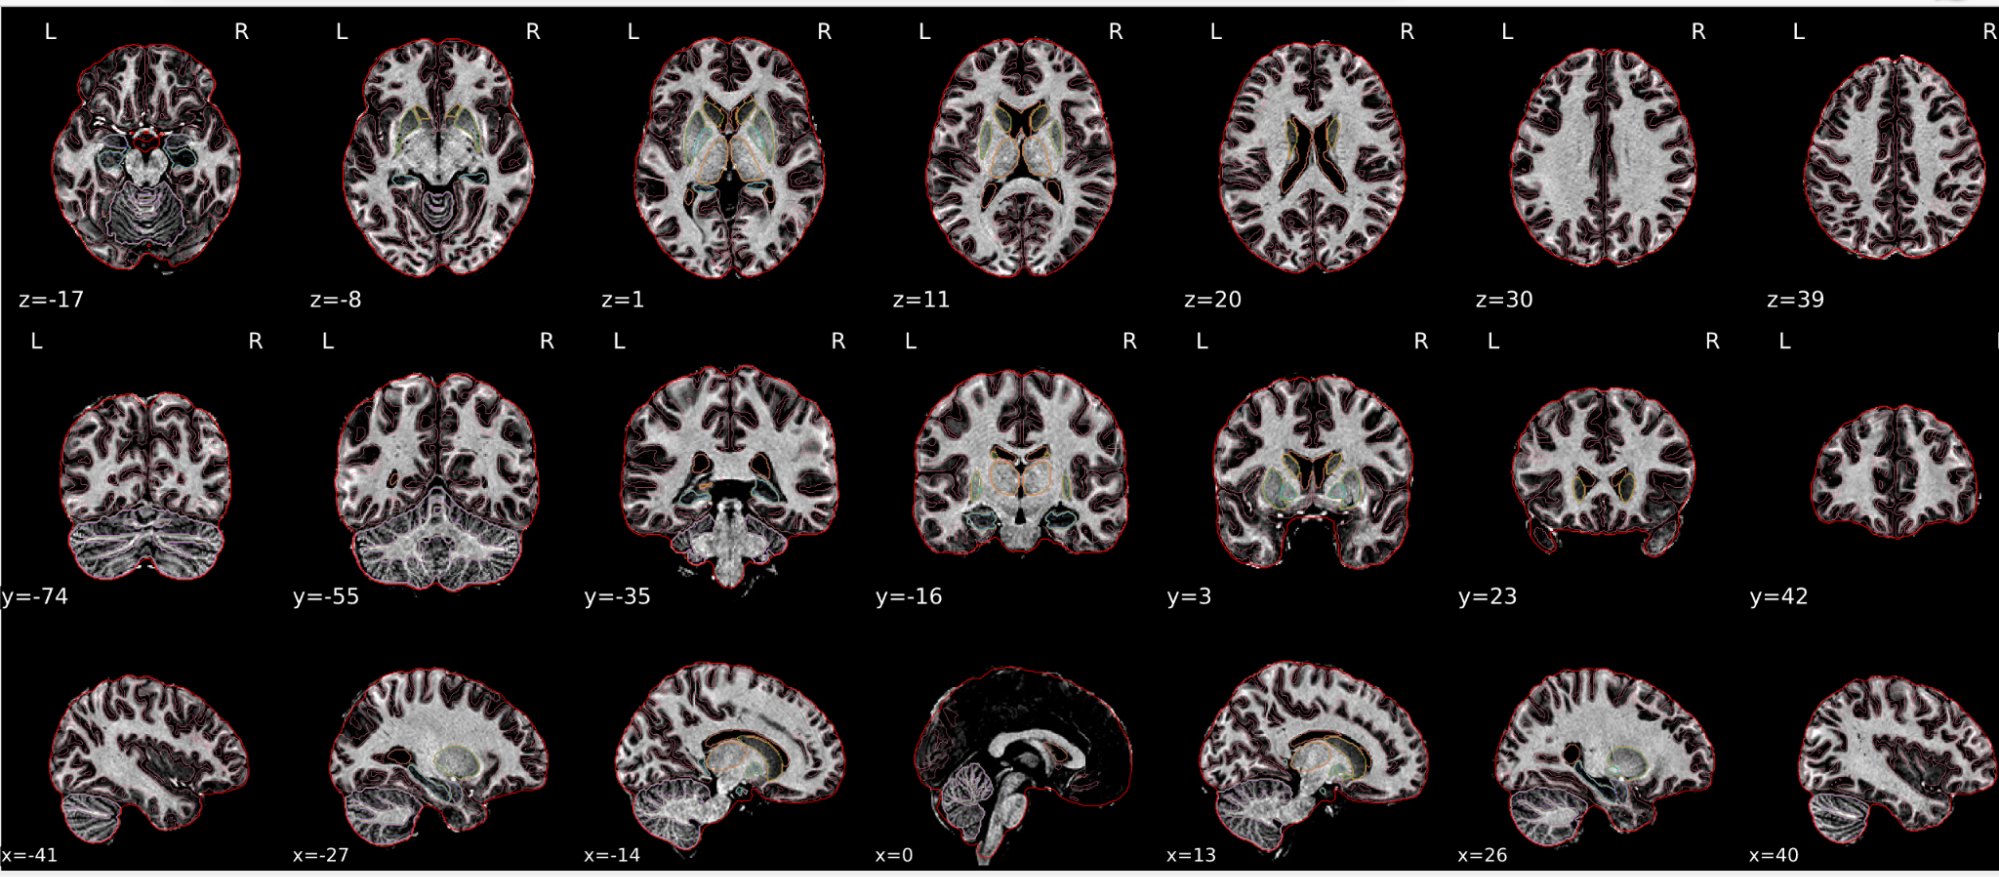

EPI spatial normalisation

This QC step shows the registration of the EPI image to MNI space.

Example of a good subject

- If the registration performed well, you should see an overlap (i.e., correspondence of structures) between the MNI template and the EPI registered to the MNI space.

- If parts of the brain are missing due to the scanner field of view, this is fine. For example, the cerebellum may be cut off for a participant with a large head.

Example of a bad subject

- In case of poor registration, you should see a misalignment of the EPI and the MNI template

Summary

| good | bad |

|---|---|

| Overlap (i.e. match of structures) between the MNI template and the EPI registered in the MNI space | Misalignment of the EPI and the MNI template |

| If parts of the brain are missing because the field of view of the scanner is limited, the EPI spatial normalisation does not have to be excluded e.g. cerebellum cut off in person with large head |

If parts of the brain are missing because the field of view of the scanner is limited, the EPI spatial normalisation does not have to be excluded (e.g. cerebellum cut off in person with large head)